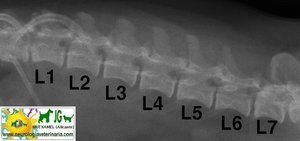

Radiografía laterolateral de la columna vertebral lumbar canina |